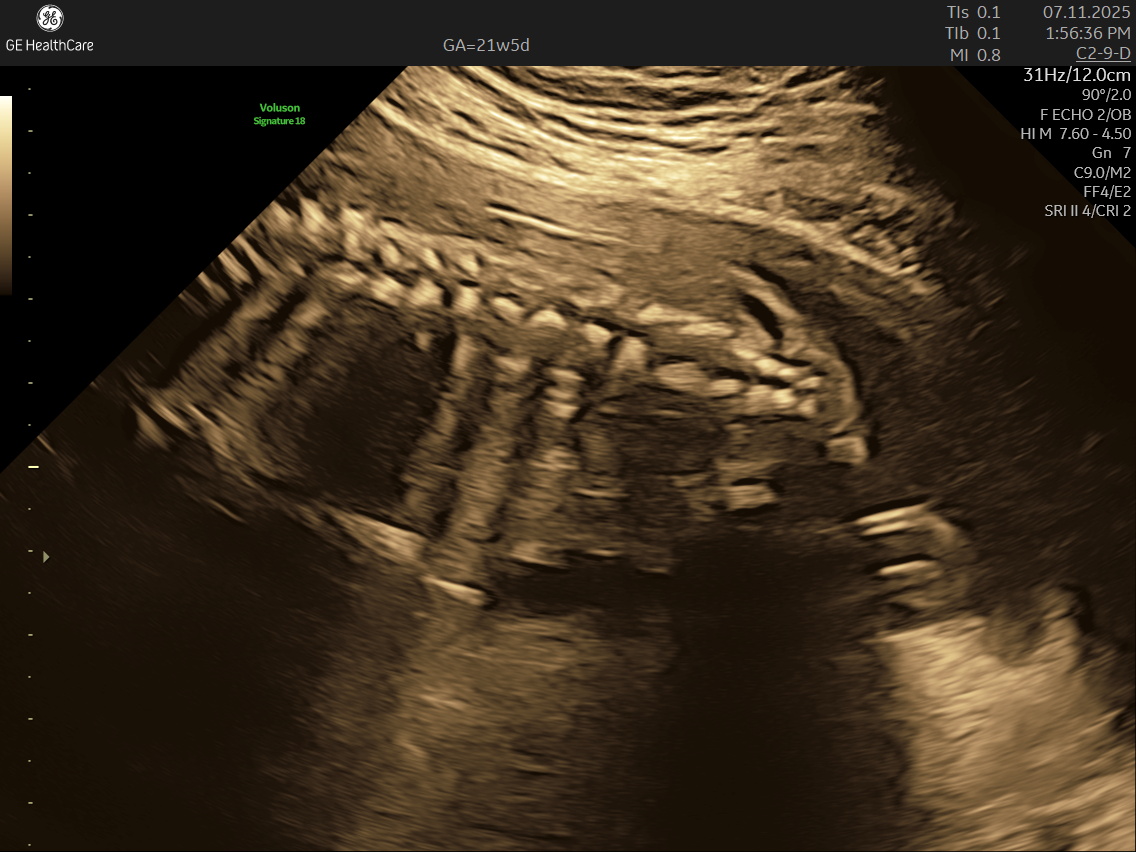

IMAGE GALLERY

If you’re expecting a baby, the Detailed Anatomy Scan —also known as the Fetal Anomaly Scan — is one of the most important checks you’ll have during pregnancy. Usually done between 18 and 22 weeks, this ultrasound is performed by highly trained fetal medicine specialists at NESA Institute of Fetal Medicine. The scan provides a close-up look at your baby’s overall development and helps to make sure everything is progressing as it should.

During this scan, the MFM specialist carries out a detailed examination of your baby’s body, checking their vital organs, spine, head, heart, limbs, and more. The aim is to confirm that your baby’s growth is on track and can identify various structural abnormalities and potential complications early, so that appropriate steps can be taken early.

• Spine and Back: Assesses alignment and formation. A healthy, well-formed spine is a crucial marker of baby’s overall development.